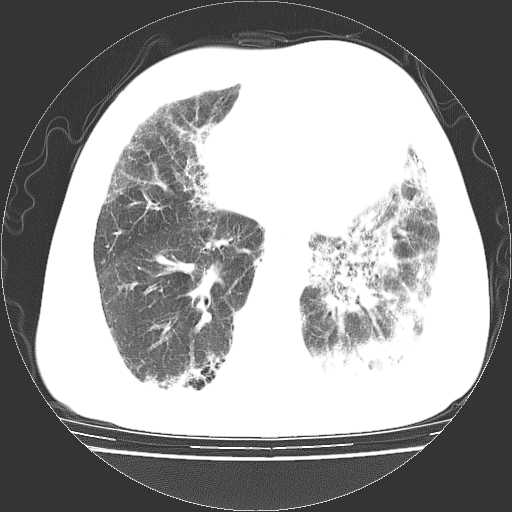

标题: CT25149:男,69岁,反复咳嗽、咳痰五年余,呼吸困难三天。 [打印本页]

男,69岁,反复咳嗽、咳痰五年余,呼吸困难三天。

慢支伴感染、肺气肿、肺心病

慢支伴感染、肺气肿、肺心病!支持!另:间质纤维化!

两肺间质性炎症并感染,左上叶肉芽肿

慢支伴感染、肺气肿、肺心病。双肺间质性改变(间质纤维化)。